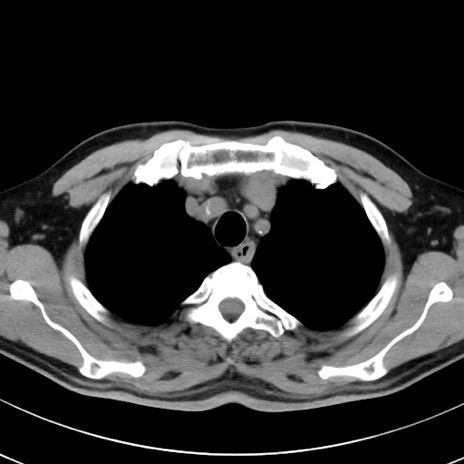

【腹部TIPS】症例29 参考症例 CT(横断像)

症例

70歳代男性